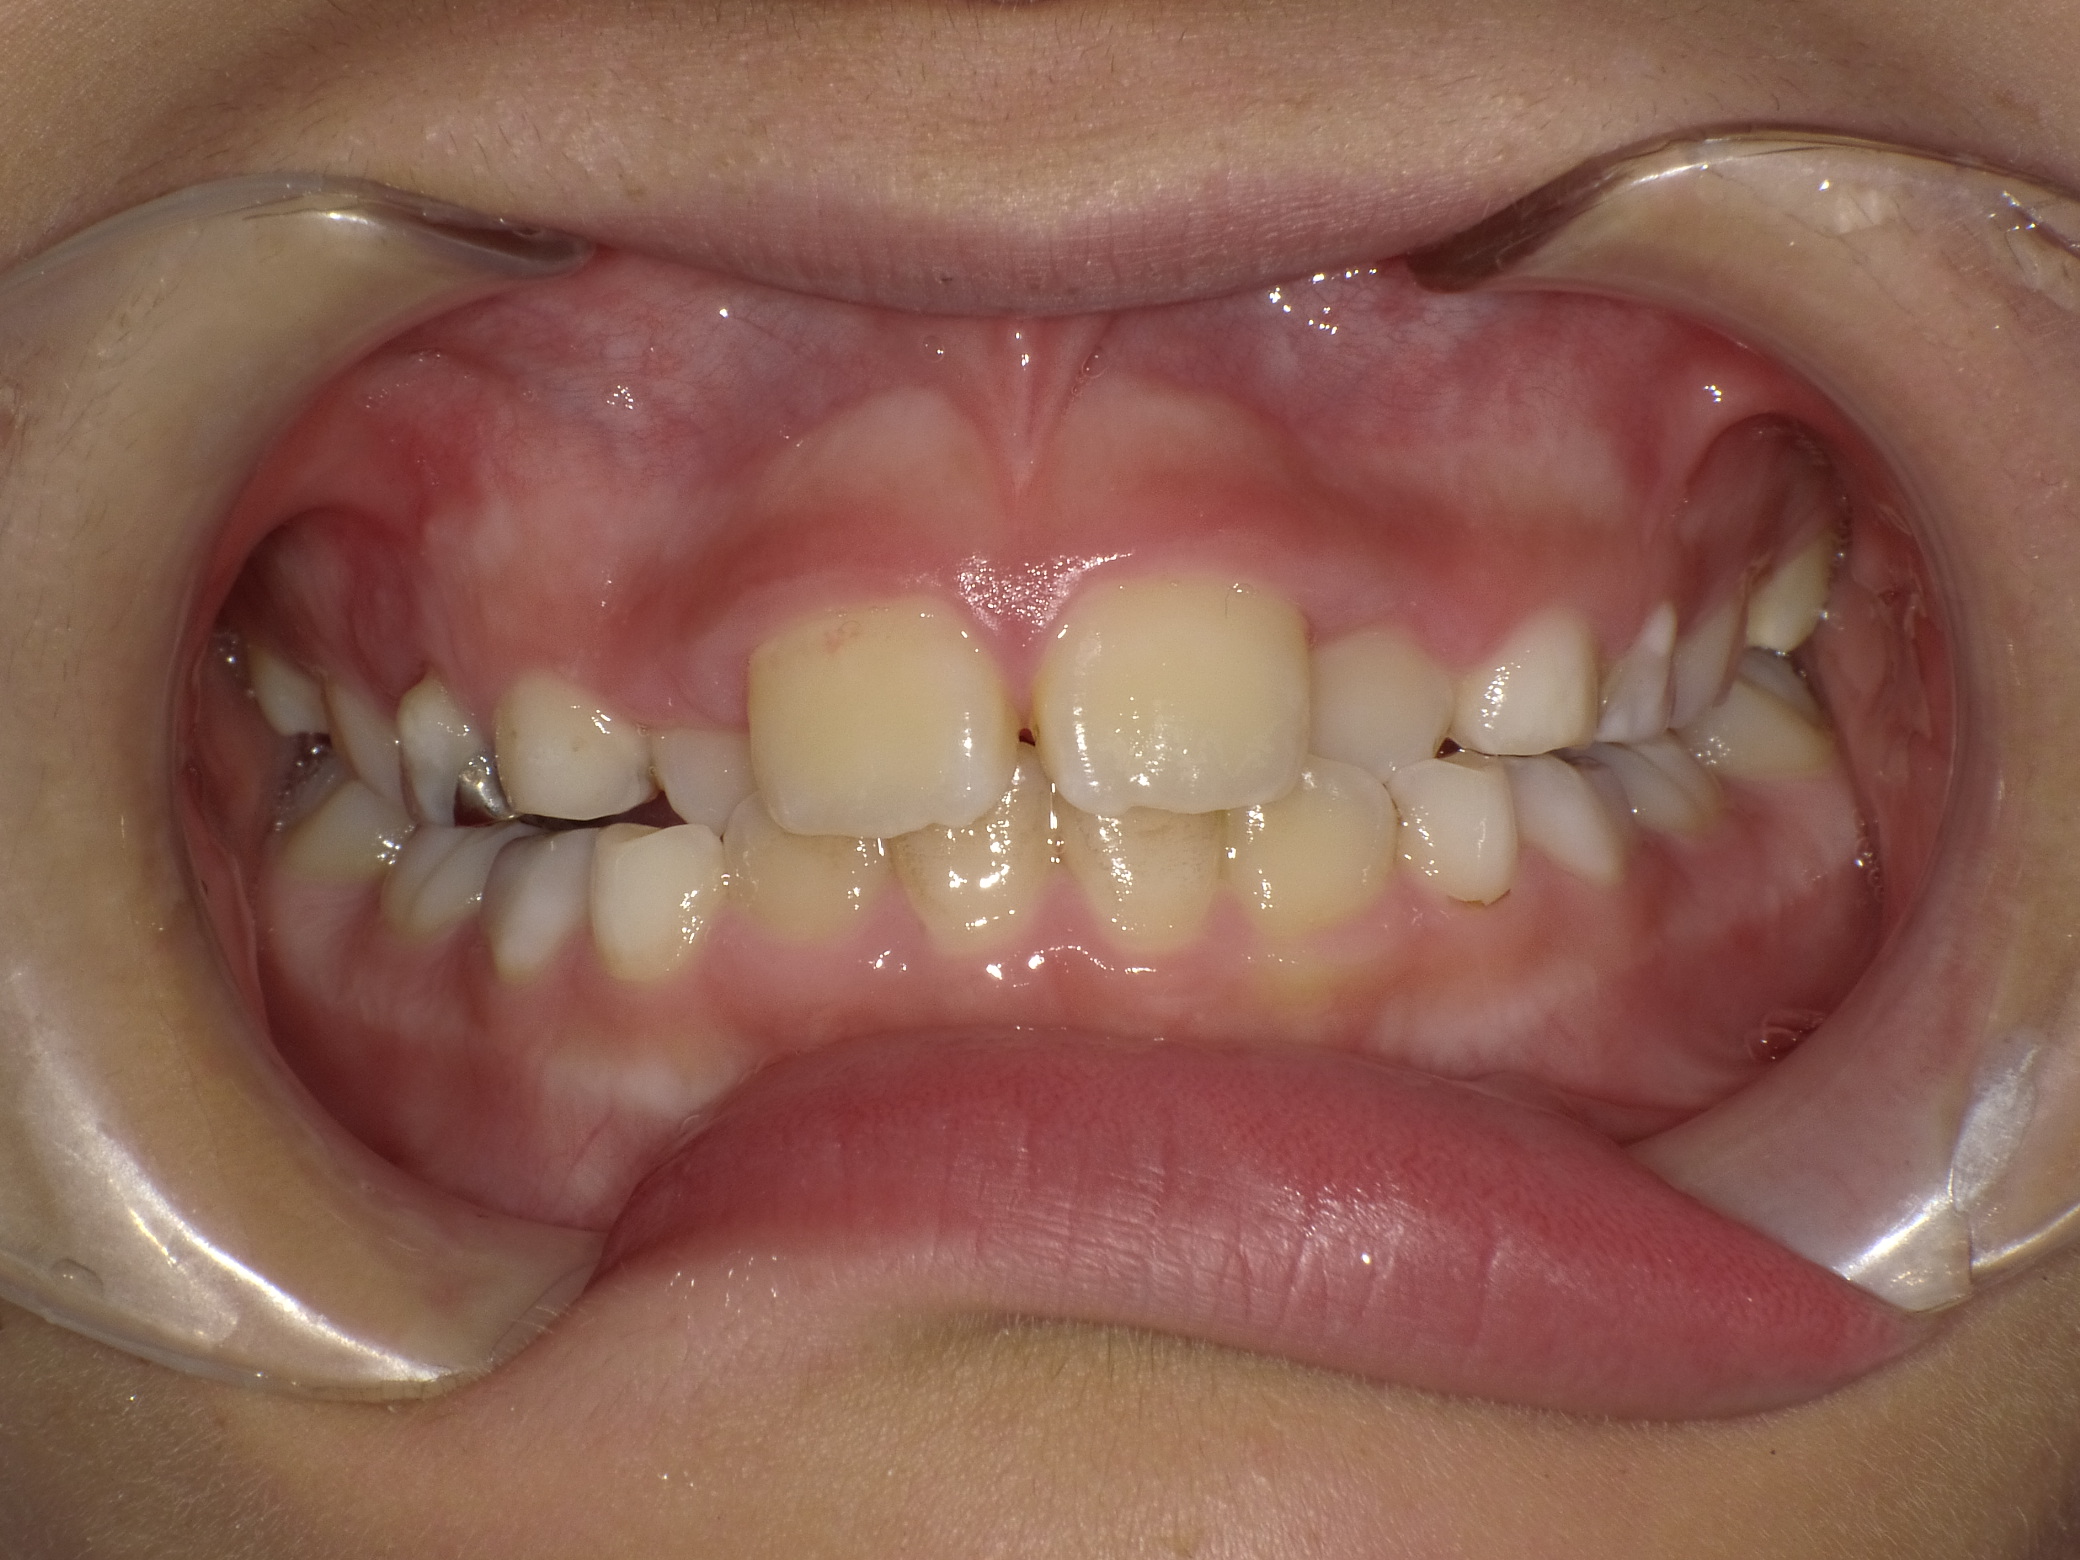

当医院ではお子様の矯正に顎の成長をサポートするような装置を使い、歯ならびを矯正します。

取り外し出来る装置のため、お子様の負担も少なく、気軽に使用できます。

当医院では歯並びだけでなく咬み合わせの確認も行っていきます。

適応年齢は小学生~中学生ですが、それ以前の年齢のお子様も定期健診で様子を診ていきますのでお気軽にご相談下さい。